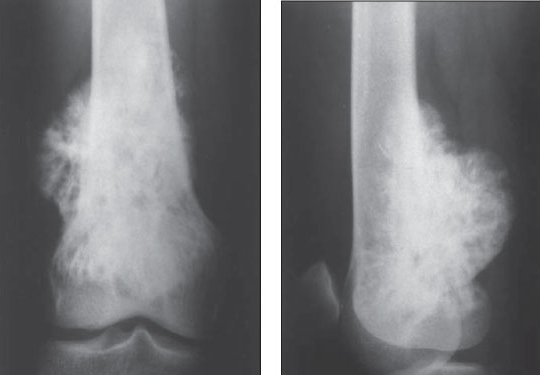

Osteosarcoma

Demographics: Occurs most commonly in the second decade of life, and a bit more commonly in boys than in girls. It occurs in all ethnic groups (in contrast, Ewing sarcoma, another bone malignancy, rarely occurs in blacks).

Symptoms: The lesion is found in the metaphyses of long bones, and usually presents with local pain and swelling.

Labs: Radiograph shows the expected “sunburst” pattern of bone formation.

Risks: Predisposing factors include a history of retinoblastoma, Li-Fraumeni syndrome, Paget disease, or radiotherapy. Any bone or joint “injury” not responding with conservative therapy within a short period of time should be evaluated.,

Osteo:

Ewing:

Over the previous 2 to 3 weeks, a very active 13-year-old white boy is noted by his family to have developed deep pains in his leg that awaken him from sleep. The family brings him to your office with a complaint of a swelling over his distal leg, which he attributes to his being kicked while playing soccer about 1 week ago. He has had no fever, headaches, weakness, bruising, or other symptoms. A radiograph of the leg is shown below. Which of the following is the most likely explanation for his pain?